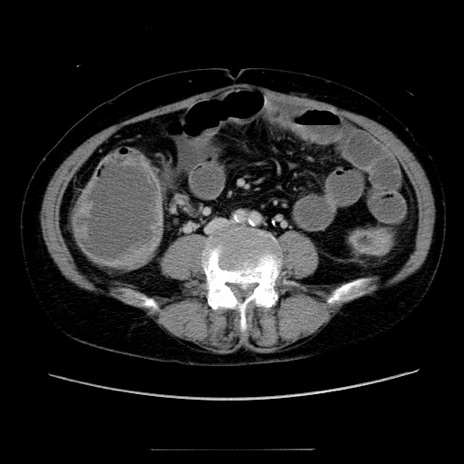

冠状断像

【症例】70歳代女性

【主訴】お腹が張る

【現病歴】1週間くらい前から腹部膨満の自覚あり。昨日夜から増悪したため、本日救急外来受診。

【身体所見】意識清明、BT 36.5℃、BP 165/106mmHg、HR 80bpm、SpO2 98%、腹部:膨満、軟、自発痛・圧痛なし、触診にて不快感あり、腸蠕動音:減弱

【データ】WBC 12600、CRP 1.04